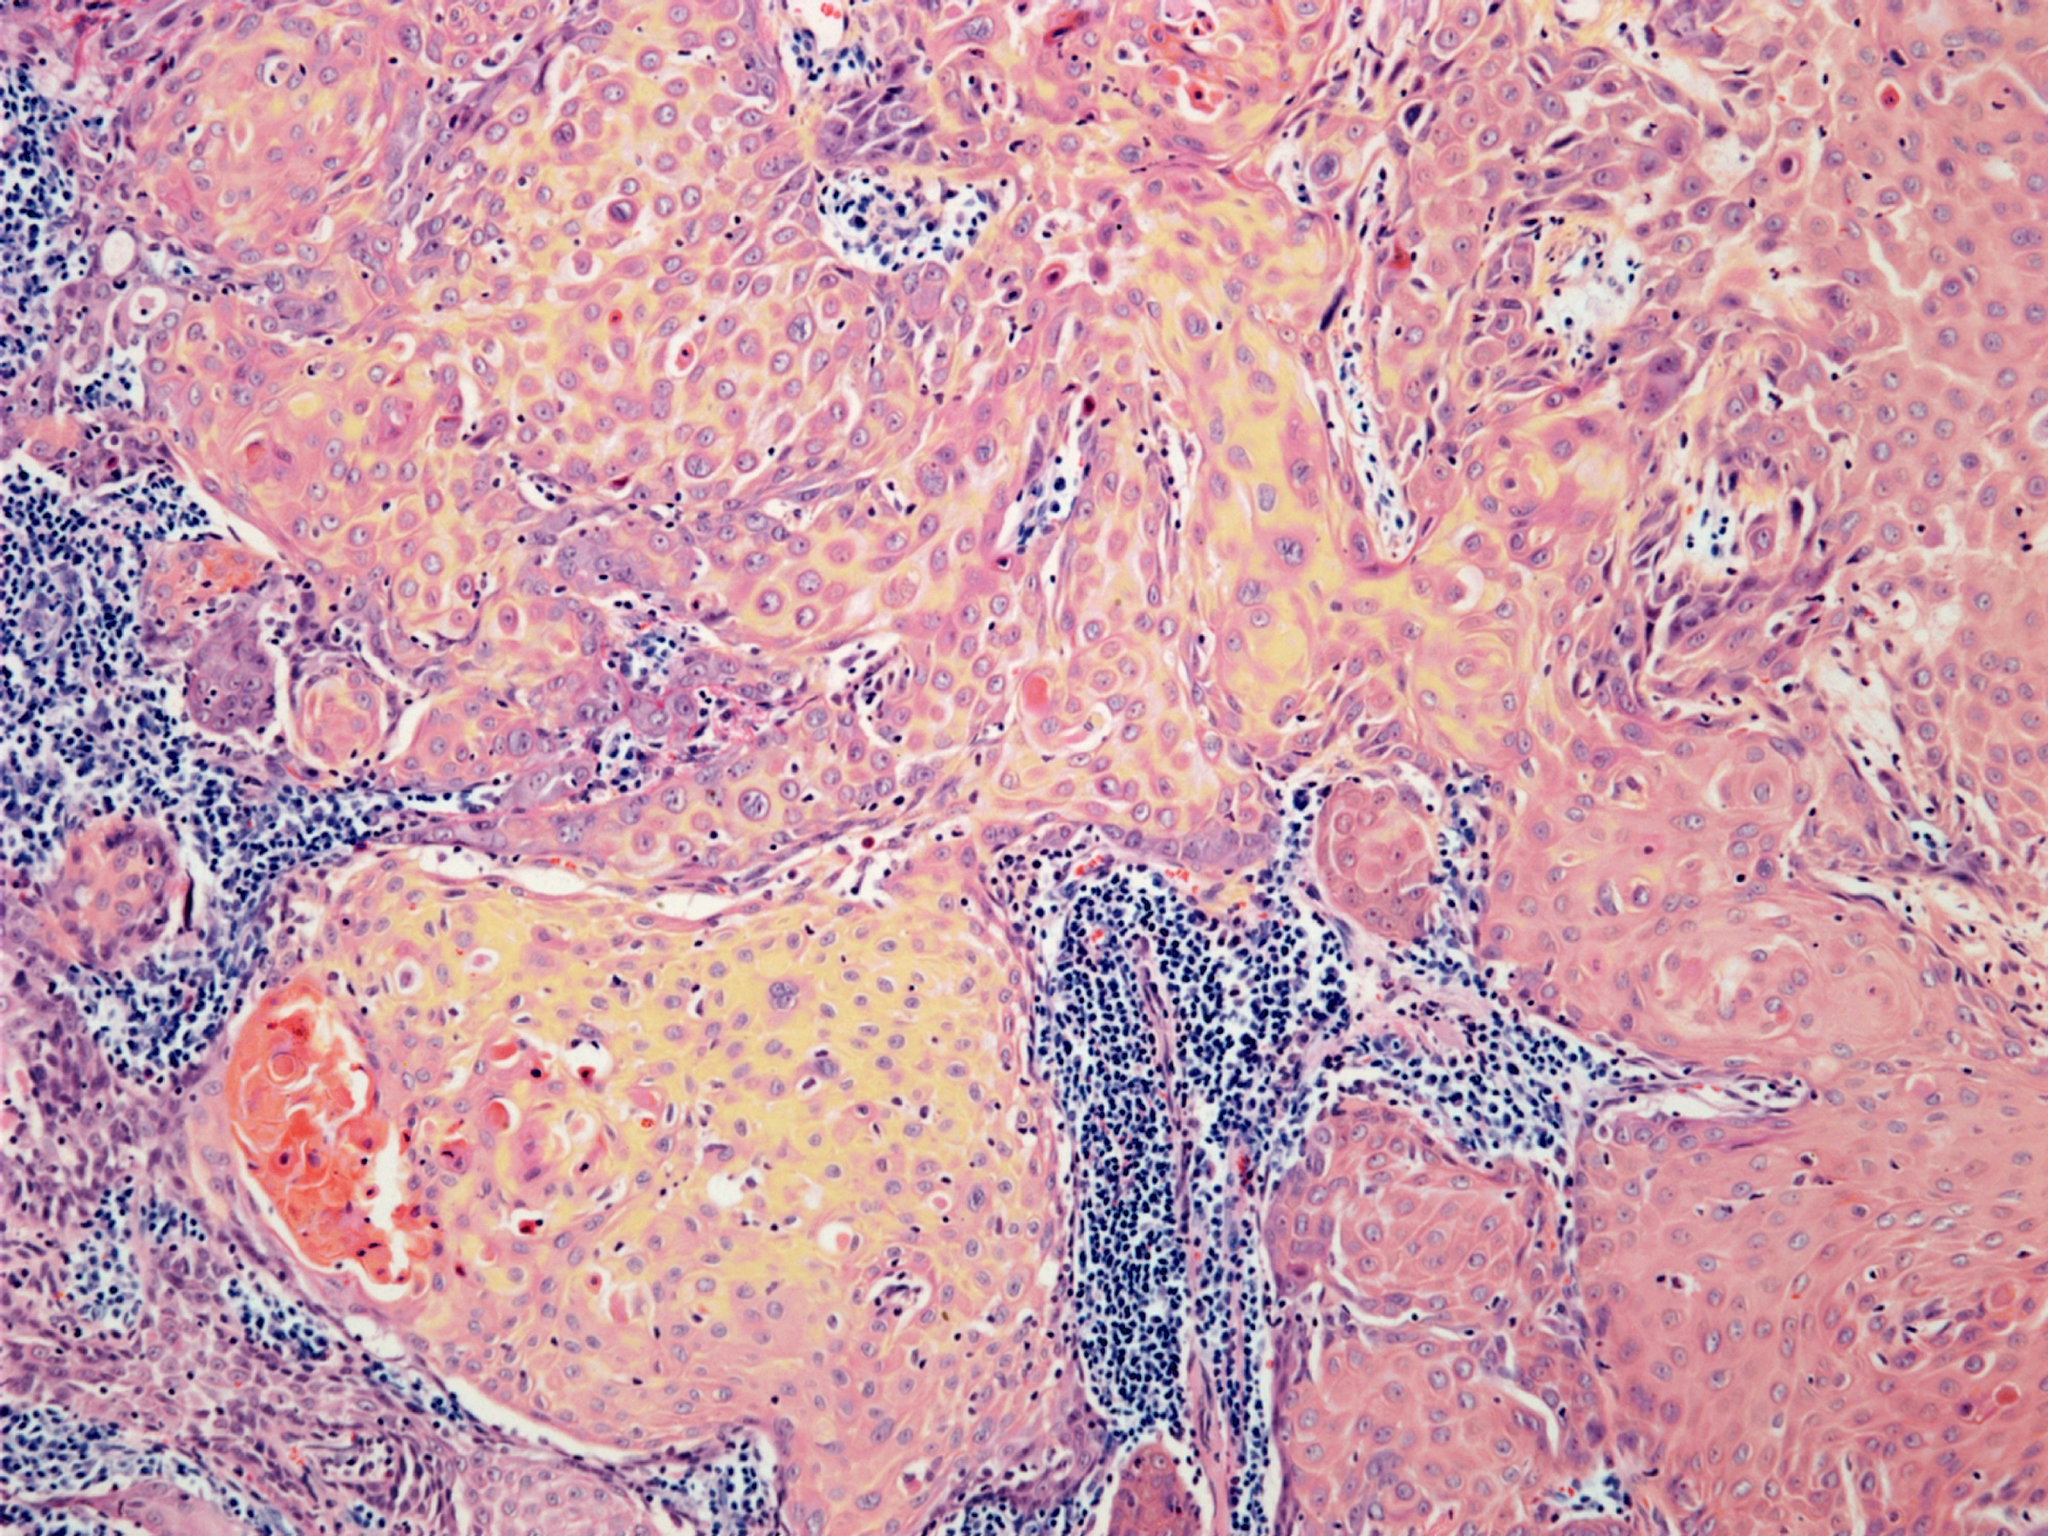

TCP病变是指体内的组织或器官发生病理性改变,其中TCP是指炎症(T),坏死(N),增生(P)和纤维化(C)的缩写。\n\nTCP病变的原因可以有多种,包括感染、损伤、自身免疫等。以下是常见的导致TCP病变的原因:\n\n1. 感染:感染引起的炎症反应可能导致TCP病变。例如,细菌感染可以引起肺炎,细菌引起的炎症会导致肺组织受损,出现坏死和纤维化。\n\n2. 损伤:组织或器官的损伤可以导致炎症反应,进而引起TCP病变。例如,心肌梗死是由于心肌血液供应中断导致的心肌损伤,损伤后的心肌组织会发生坏死和纤维化。\n\n3. 自身免疫:自身免疫疾病是免疫系统错误地攻击自身组织的情况,可能导致TCP病变。例如,类风湿性关节炎是一种自身免疫性疾病,免疫系统攻击关节组织导致炎症、坏死和纤维化。\n\nTCP病变的具体表现会根据病变的部位和严重程度而有所不同。一般来说,炎症会导致局部红肿、疼痛和功能障碍;坏死会导致组织死亡和功能丧失;增生会导致组织细胞增加,可能形成肿块或增生性病变;纤维化会导致组织纤维成分增多,丧失原有的结构和功能。具体的症状和影响因病变的部位和严重程度而异。